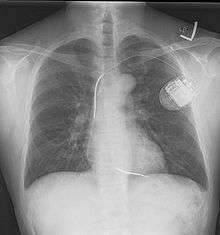

A chest film after insertion of an implantable cardioverter-defibrillator, showing the shock generator in the upper left chest and the electrical lead inside the right heart. Note both radio-opaque coils along the device lead.